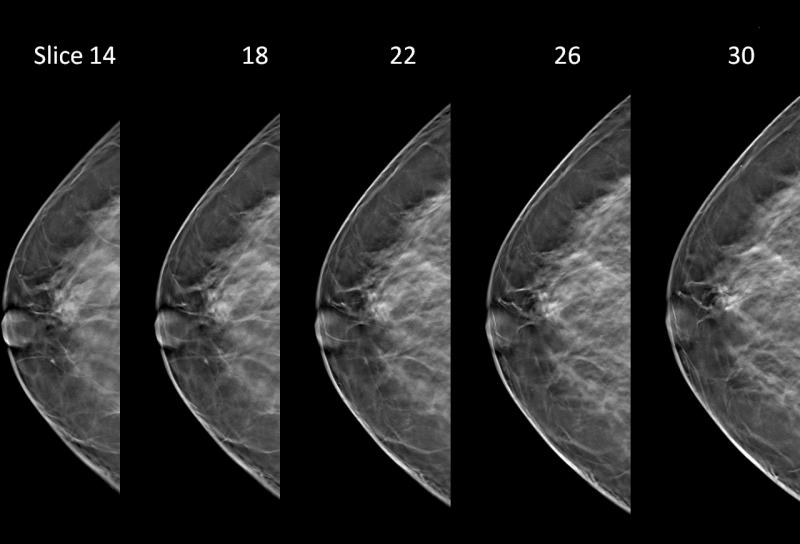

In the 2D image on we are looking at a potential lesion in the subareolar region of the breast.

Prominently featured at RSNA this year is Hologic's Selenia Dimensions 3-D mammography (breast tomosynthesis) system. The technology was approved by the U.S. Food and Drug Administration (FDA) in February 2011 and has been available in countries recognizing the CE mark since 2008. Hologic's 3-D mammography technology is available in 47 states in the United States and 28 other countries.

Some of Hologic's other advances in breast tomosynthesis on display at the conference included its tomosynthesis biopsy option for use with the Affirm biopsy guidance system and its C-View synthesized 2-D image option. The tomosynthesis biopsy option is CE marked and is pending FDA clearance. C-View images are designed to be used with tomosynthesis in the screening and diagnosis of breast cancer, eliminating the need for a separate 2-D exposure. The C-View synthesized 2-D image option received CE marking in 2011 and while not yet approved in the United States, received a favorable vote from an FDA Advisory Panel in October 2012.